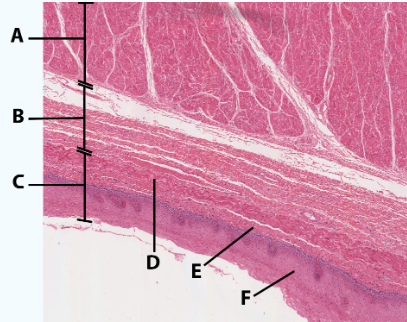

A

Muscularis

B

Submucosa

C

Mucosa

D

Muscularis mucosa

E

lamina propria

F

stratified squamous epithelial tissue

area

Esophagus